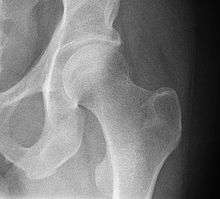

Radiograph of a healthy human hip joint

The hip joint is a synovial joint formed by the articulation of the rounded head of the femur and the cup-like acetabulum of the pelvis. It forms the primary connection between the bones of the lower limb and the axial skeleton of the trunk and pelvis. Both joint surfaces are covered with a strong but lubricated layer called articular hyaline cartilage. The cuplike acetabulum forms at the union of three pelvic bones — the ilium, pubis, and ischium.[5] The Y-shaped growth plate that separates them, the triradiate cartilage, is fused definitively at ages 14–16.[6] It is a special type of spheroidal or ball and socket joint where the roughly spherical femoral head is largely contained within the acetabulum and has an average radius of curvature of 2.5 cm.[7] The acetabulum grasps almost half the femoral ball, a grip augmented by a ring-shaped fibrocartilaginous lip, the acetabular labrum, which extends the joint beyond the equator.[5] The head of the femur is attached to the shaft by a thin neck region that is often prone to fracture in the elderly, which is mainly due to the degenerative effects of osteoporosis.

The angle between the longitudinal axes of the femoral neck and shaft, called the caput-collum-diaphyseal angle or CCD angle, normally measures approximately 150° in newborn and 126° in adults (coxa norma).[13]

An abnormally small angle is known as coxa vara and an abnormally large angle as coxa valga. Because changes in shape of the femur naturally affects the knee, coxa valga is often combined with genu varum (bow-leggedness), while coxa vara leads to genu valgum (knock-knees).[14]

Changes in CCD angle is the result of changes in the stress patterns applied to the hip joint. Such changes, caused for example by a dislocation, changes the trabecular patterns inside the bones. Two continuous trabecular systems emerging on auricular surface of the sacroiliac joint meander and criss-cross each other down through the hip bone, the femoral head, neck, and shaft.